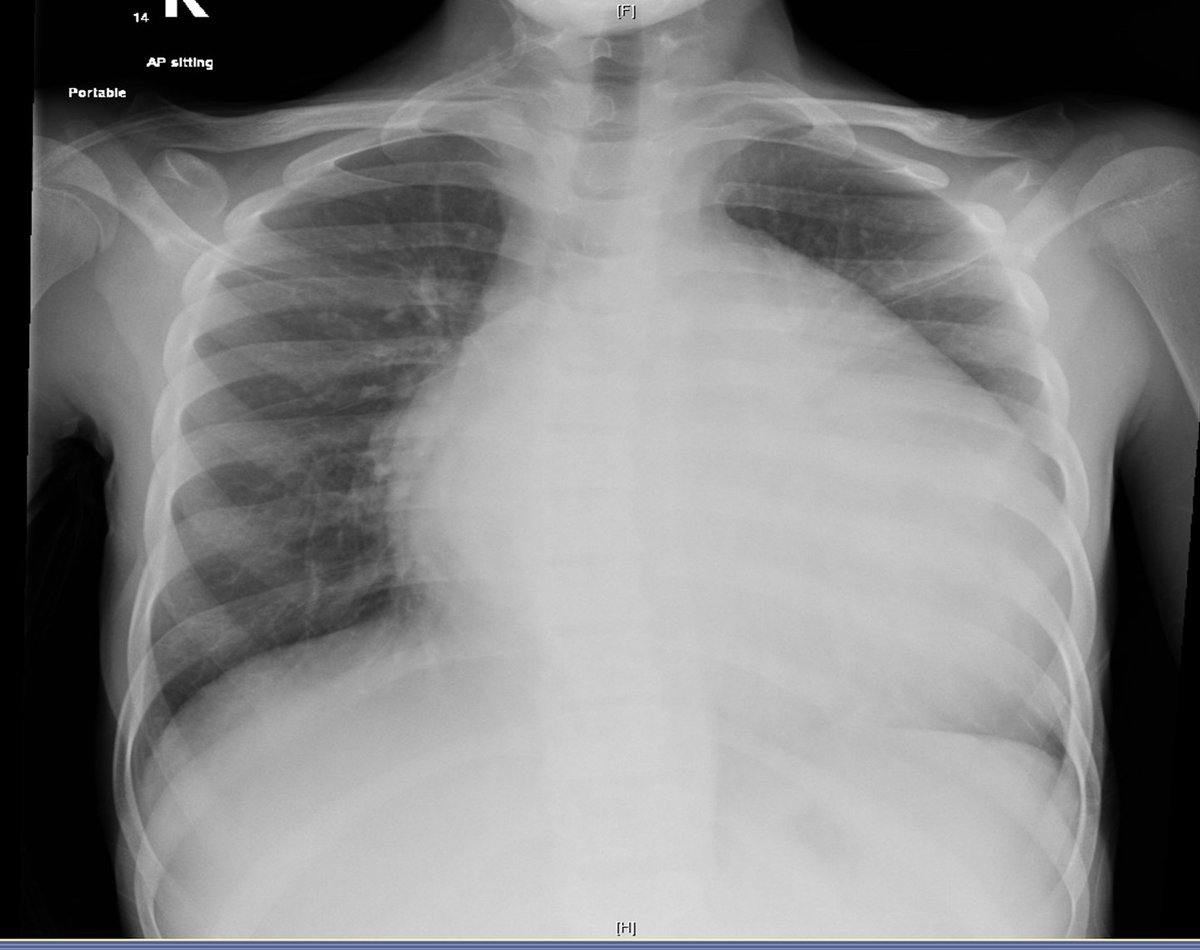

14 male with severe SOB.

THE ECHO didnot reveal any pericardial effusion.

BNP 3395, Normal Below 29.

Severe dilated cardiomyopathy.